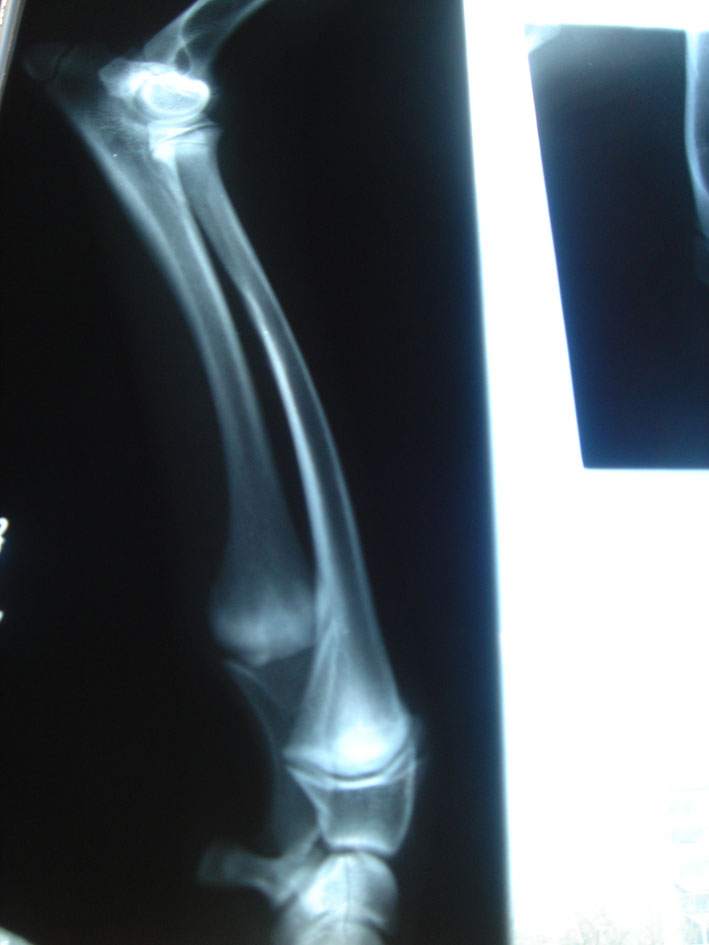

AZAWAKH ARA N'TATRIT a dog with a Radius Curvus Syndrom.